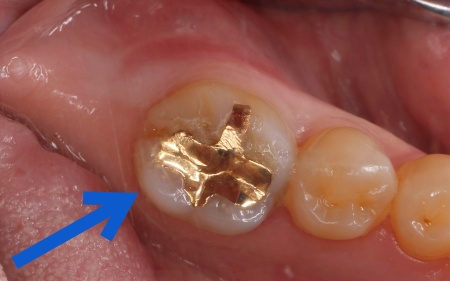

| 診断 | 拝見したところ、右下奥歯の一部が欠けている状態でした。 長期間にわたり噛む力が繰り返し加わったことで、奥歯に負担が蓄積して欠けてしまったと考えられます。 このまま放置すると、欠けた部分から細菌が侵入して虫歯が進行したり、ひびが広がって亀裂が深くなり、最終的には歯の温存が難しくなったりするおそれがあります。 以上のことから、歯を適切に保護し、これ以上ダメージが広がらないようにする治療が必要だと診断しました。 |

| 行ったご提案・治療内容 | 患者様は「周囲の歯になじむ自然な見た目で、長く安心して使える治療をしたい」と希望されていたため、通常の詰め物よりも広い範囲を覆う「オンレー」という修復方法を提案し、同意いただきました。

オンレーは、歯全体を覆う被せ物と比べると歯を削る量を抑えられるため、健康な歯をできるだけ残しながら、歯の強度を高めることが可能です。ただし、歯の状態によっては適応できない場合もあります。 まず、すでに装着されていた金属の詰め物を除去し、歯の状態を慎重に確認します。 次に、採取した歯型をもとにオンレーを作製します。 最後に、完成したオンレーを専用の接着剤で装着し、見た目や噛み合わせに問題がないことを確認して、治療を終了しました。 患者様の上の歯の治療についてはこちら:https://dr-kaiya.com/blog/20260312-1/ |

治療前